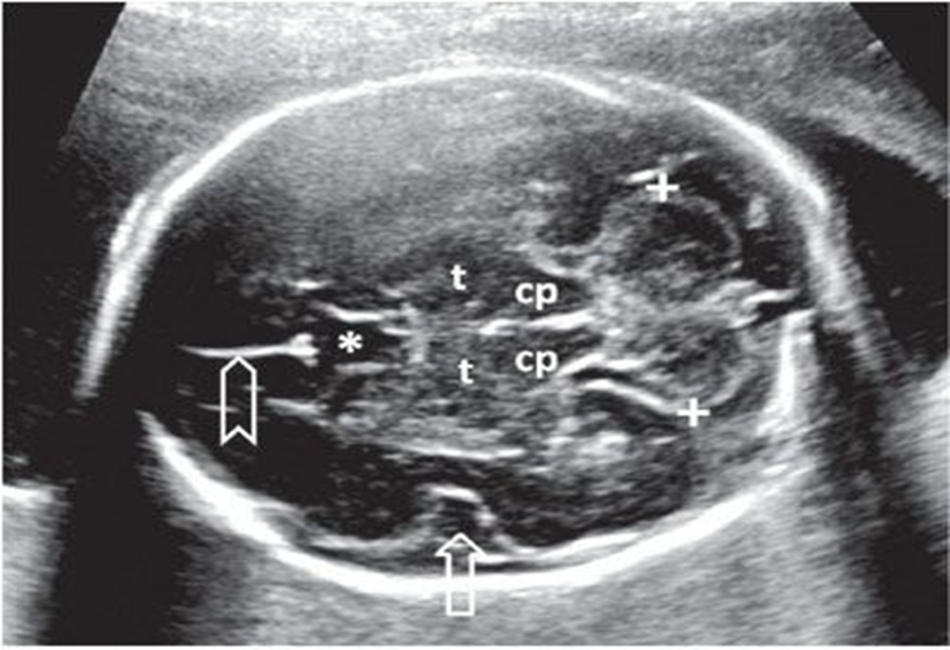

calipers of choroid plexus and lateral ventricles

inner to inner

measure _____ portion of lateral ventricle through the most _____ portion of choroid plexus

posterior, posterior

back of brain / posterior fossa includes

cerebellum, cisterna magna, vermis, 4th vent, cerebral peduncles, brainstem, and tentorium